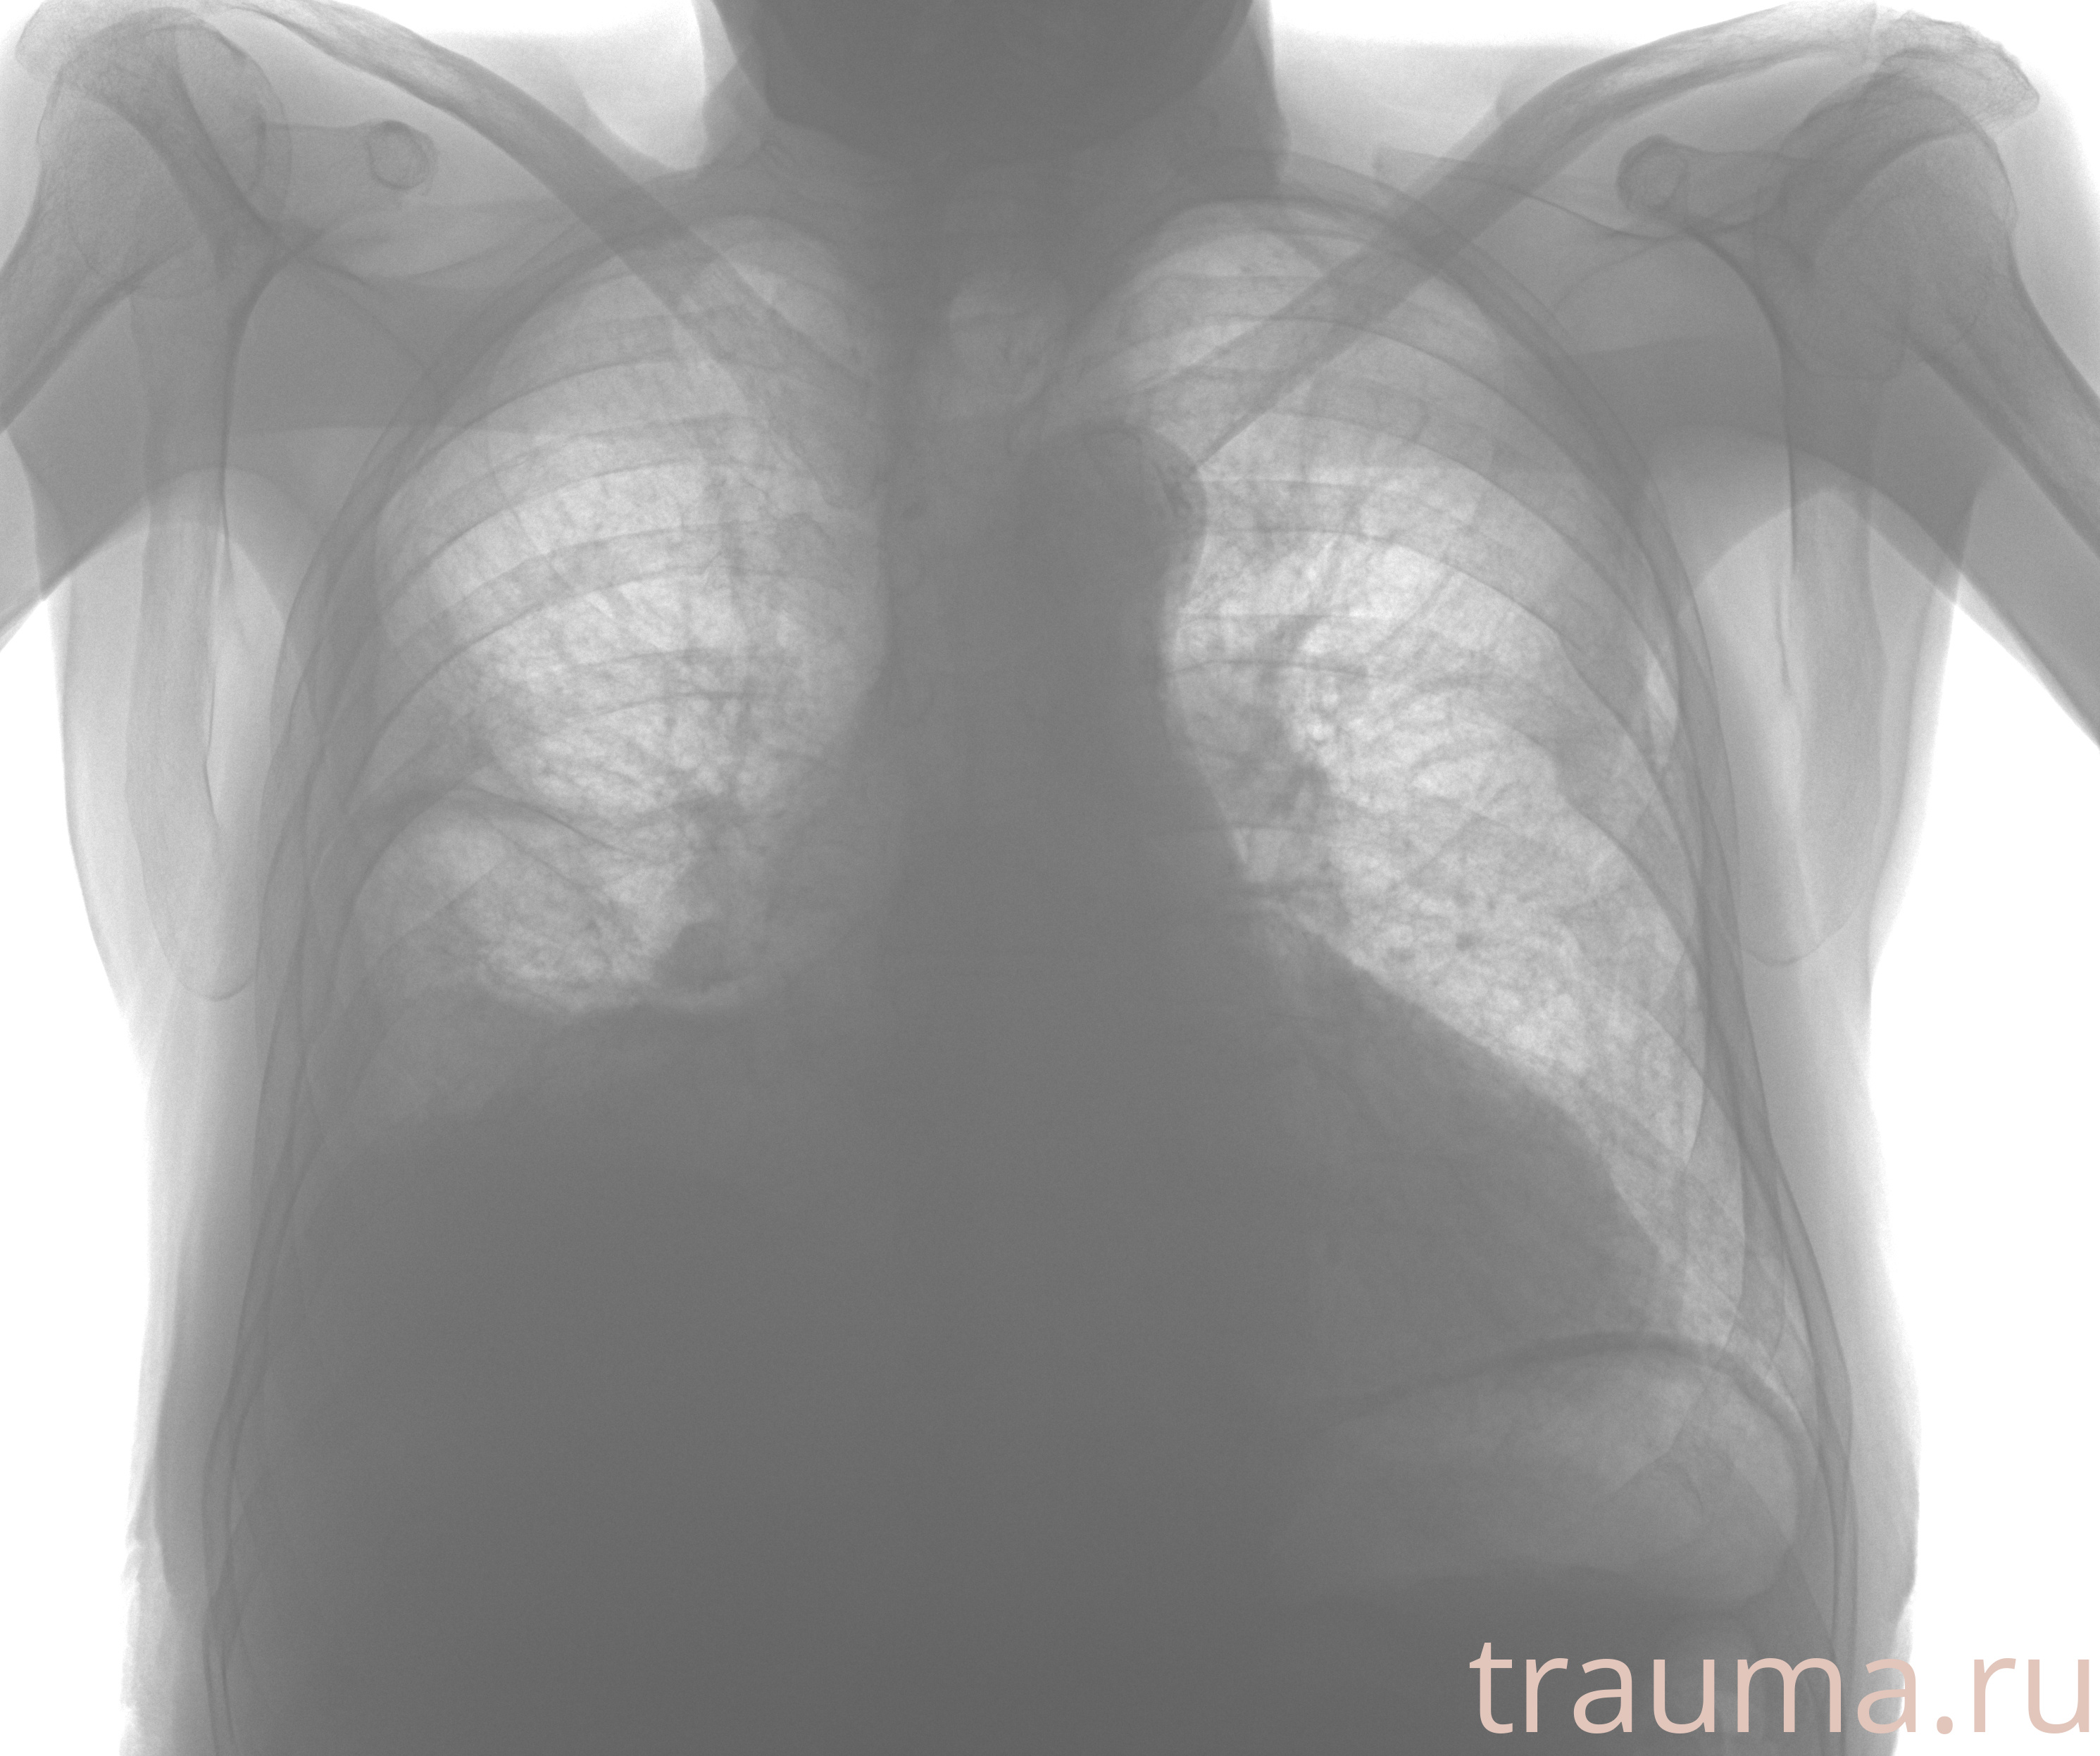

Рентген на дому: по вашему адресу приезжает врач-рентгенолог, травматолог-ортопед с мобильным рентгеновским аппаратом, проводит диагностику травмы или заболевания, делает необходимые рентгенограммы, дает рекомендации по дальнейшему лечению. Получить качественные снимки в домашних условиях возможно благодаря уникальной методике, разработанной МосРентген Центром для института  Склифосовского

при переломе шейки бедра и пневмонии от компании МосРентген Центр - партнера Института имени Склифосовского